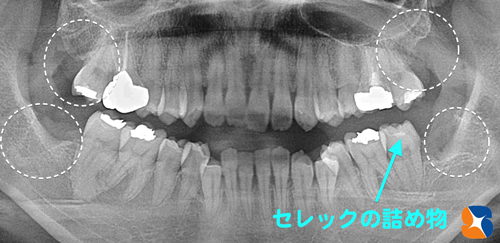

傾く右下の親知らずを除けば、残りの親知らず3本は、傾くことなく真っすぐ生えていました。これなら、患者様の要望通り、4本の親知らずの抜歯とむし歯の治療をまとめてさせて頂けると判断しました。

本日、2度目の来院。出血も落ち着いていたので、早速セレックを虫歯の部分をスキャン(ビデオ撮影)しました。

パソコン画面で虫歯の詰め物(オールセラミック)の設計を行いました。

無事にオールセラミックの詰め物が、抜いた親知らずの手前の歯に接着させる事が出来ました。

親知らずの4本抜歯とオールセラミックの詰め物の治療を無事に一日で完了させることが出来ました。